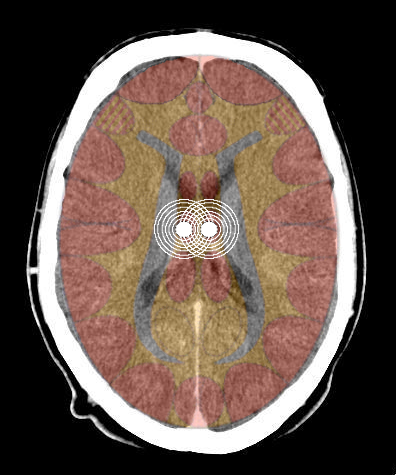

- Requisiti: Si è in costellazione schizofrenica quando due attivazioni colpiscono i due emisferi cerebrali di uno stesso livello:

- le due emiparti del tronco cerebrale;

- i due emisferi cerebellari;

- i due emisferi cerebrali (midollo e/o corteccia).

- Relè cerebrali: Due SBS a livello cerebellare

- Relè cerebrali: Due relè nella sostanza bianca cerebrale;